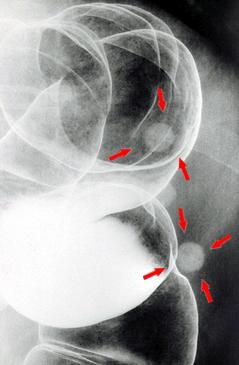

粘膜下腫瘍様の所見を呈した大腸壁ないし腸管外の石灰化病変のX線像

疾患(病理主体)の分類腫瘍様病変/その他

部位(臓器別)大腸/下行

検査方法X-P

病変の最大径(ミリ)10〜14

多発腫瘍(同一臓器)有(同時性)